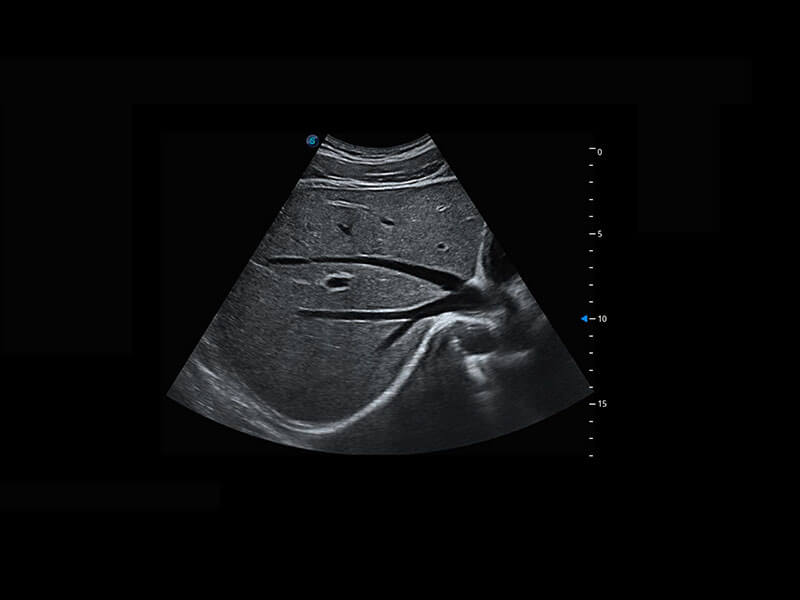

P60优异的图像质量搭载专科探头,在妇科基础疾病的诊断、卵泡生长的监测、输卵管通畅情况的判别等方面为您提供生殖应用方案。

腔内妇科-宫腔分离

腔内妇科-卵巢

腔内三维-宫内节育器

腔内三维-光影成像